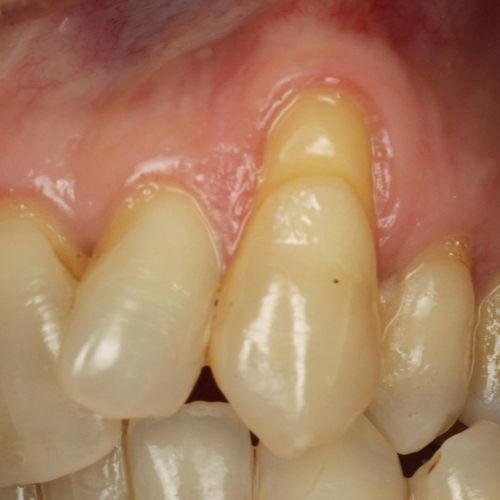

| Before and after surgery to reshape gums | X-ray showing results before and after bone graft surgery |

| Free gingival graft surgery’ to thicken gum and prevent further recession | Gum recession surgery in an aesthetic site |